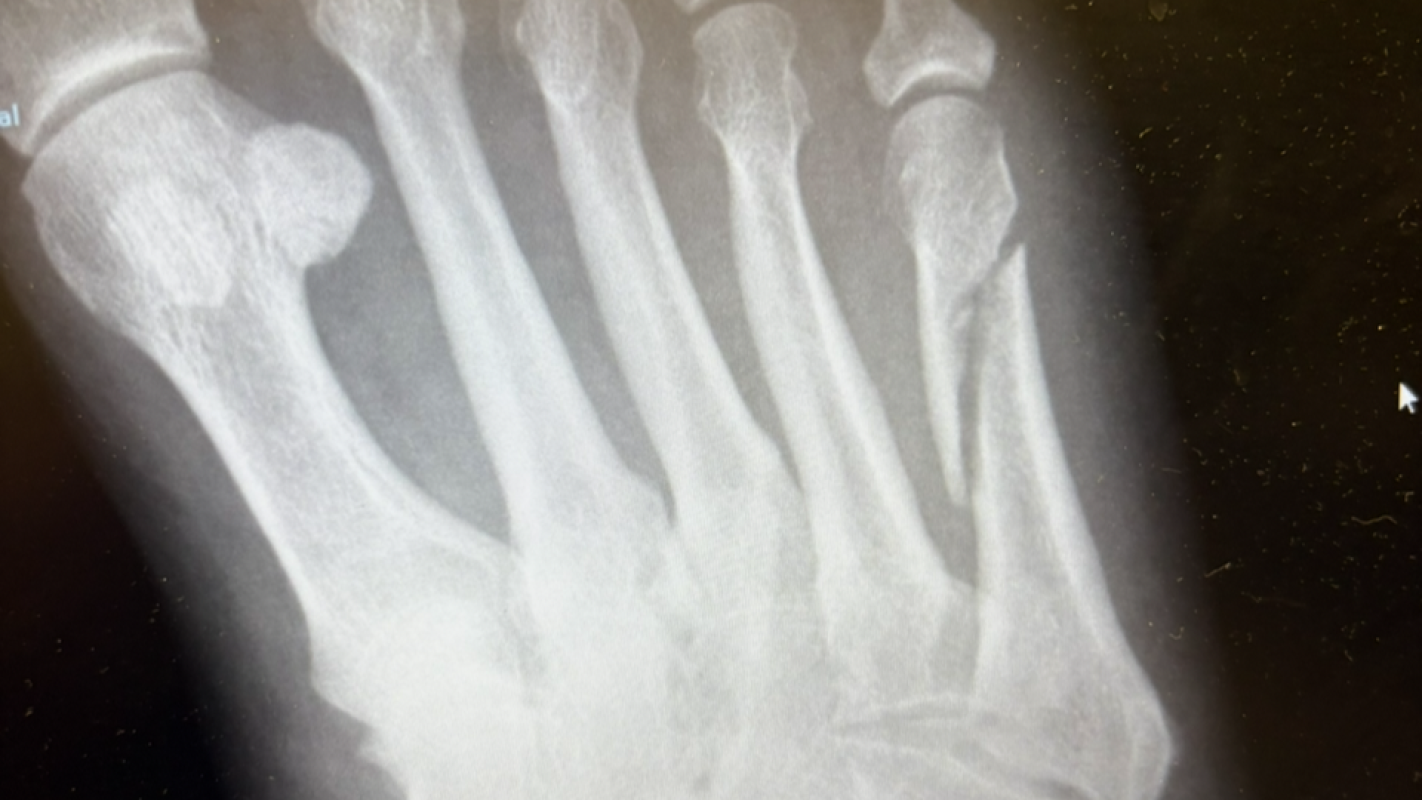

I have had a hand injury and unable to work to pay my Bills and stay on top of them asking for a little bit of help, so I don't fall into a hole. As ofinjury and unable to work to pay my Bills and stay on top of them asking for a little bit of help, so I don't fall into a hole. As of one bill keep me out of jail im just ask for some help is all and not bixby expecting anything thank you , and it is great for you to appreciate it if helped